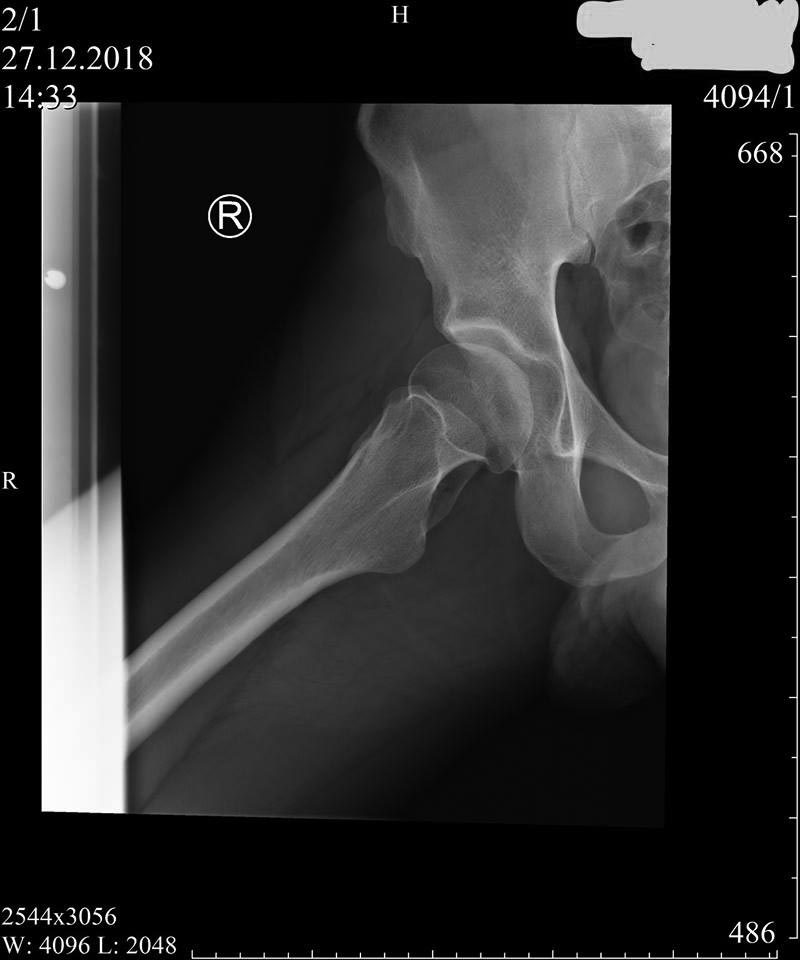

Пациент 27 лет: с 14-ти - "щёлканье" в тазобедренных суставах...

Последние полгода - боль (особенно после вставания из положения сидя),

которая устраняется "встряхиванием" ноги (правой) со "щелчком"...

Владимир Георгиевич Босых (профессор МГМСУ) полагает, что на

рентгенограммах: "ярко выраженный подвывих бедра и в зависимости от

клиники надо ставить вопрос о хирургической коррекции (возможно, тройной

остеотомии таза)".